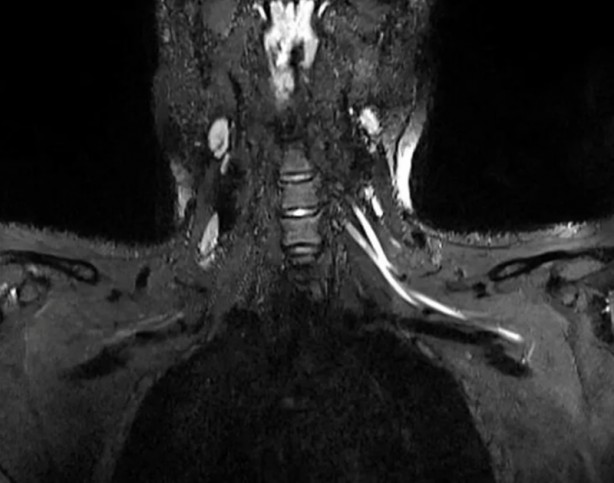

Bilim insanları yeni tip koronavirüs (Covid-19) hastalarında görülen yorgunluk ve ağrının sebebini ilk kez ortaya koydu. ABD’de yer alan Northwestern Üniversitesi’nden araştırmacılar MRI ve ultrason tekniklerini birleştirerek, geleneksel yöntemlerle tespit edilemeyen Covid-19'un sinir sisteminde yarattığı hasarı kanıtladı. Geliştirilen yeni teknolojinin doktorlara, hastaları için uygun tedavi yöntemini belirlemesini sağlayarak hayat kurtarabileceği belirtildi.

Radiology dergisinde yayımlanan çalışmanın başyazarı Doktorlar Ağrı boynunuzdaki, dirseğinizdeki veya bileğinizdeki sorunlardan kaynaklanıyor olabilir ve bunu anlamanın en iyi yolu MRI veya ultrasondur. Yaptığımız çalışmayla çok küçük sinirleri bile gösteren gelişmiş görüntüleme sunuyoruz. Bu da sorunun nerede olduğunu tespit etmemize, ciddiyetini değerlendirmemize ve buna neyin neden olabileceğini önermemize yardımcı olabilir.

KORONA SİNİR SİSTEMİNDE ŞİDDETLİ İLTİHAPLANMAYA NEDEN OLABİLİR Bununla birlikte Doktor Deshmukh, koronavirüsün aşırı bağışıklık tepkisini tetiklemesinden dolayı, vücut tarafından üretilen antikorların sadece enfekte hücrelere değil, sağlıklı dokulara da saldırmaya zorlayarak ciddi semptomlara neden olduğunu söyledi. Bilim insanı, olayın ardından sinir sisteminde de şiddetli iltihaplanma görülebileceğini açıkladı.

DOKTORLARIN UYGUN TEDAVİ İÇİN KARAR VERMESİNİ KOLAYLAŞTIRACAK Öte yandan, çalışmanın yazarları gelişmiş ultrason teknolojisinin kolay taşınabilir ve ucuz olduğunu, ayrıca sinir hasarını tespit etmede tomografiden daha iyi olduğunu ifade etti. Araştırmacılar, taramaların doktorların hastaları bir rehabilitasyon uzmanına mı yoksa daha ciddi durumlarda bir cerraha mı sevk edeceklerine dair karar vermelerine yardımcı olacağını aktararak, “Eğer görüntüleme enflamatuar bir tepkiye bağlı sinir hasarı bulursa, hastaya bir nöroloğa görünerek daha iyi hizmet edilebilir. Görüntüleme, hematomdan kaynaklanan sinir hasarını ortaya çıkarırsa, kan sulandırıcı ilaçların derhal ayarlanması gerekir ve hatta hastanın bir cerrahı görmesi gerekebilir” açıklamasını yaptı.